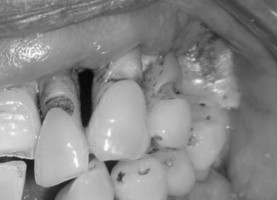

Advanced gum disease, also called periodontitis, is caused by bacterial infection that damages the soft tissue and bone that support the teeth. Previous research has shown a link between periodontitis and increased cancer risk, although the mechanism connecting the two diseases is under investigation, as the following study reports.

The dental exams provided detailed measurements of the depth of the pocket between the gum and tooth in several locations in the mouth.